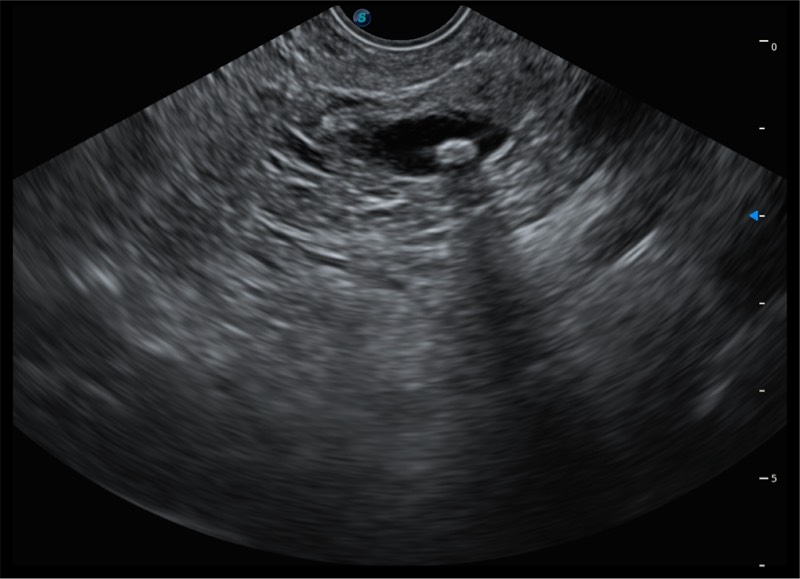

搭载百万级CMOS成像技术

及自主研发凸阵换能器,

可呈现优质的内镜和超声画面

基于二十年的超声技术积累,诸侯快讯官网提供了最新一代的独立超声主机,在提供高质量图像的同时满足多学科使用。具备常见多普勒技术并提供弹性成像、声学造影等高端影像技术。新一代传感器具有更强的抗干扰能力并减少图像伪影。

150°超声扫描角度

4-12MHZ宽频输出